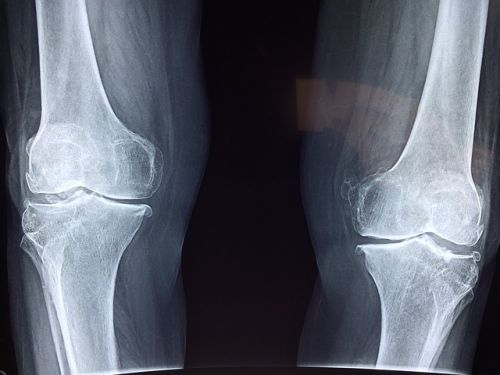

다음으로 질환 조건입니다. 일반적인 무릎 통증이 아닌, 건강보험급여 ‘인공관절치환술(슬관절)’ 인정기준에 해당되는 진단을 받아야 합니다. 다시 말해, 단순한 통증이나 타박상으로는 안 되고, 정형외과에서 ‘퇴행성 관절염’, ‘심한 무릎연골 마모’ 등으로 인해 인공관절 수술이 필요하다는 소견이 나와야 하는 거죠. 이 소견은 반드시 의사의 진단서 또는 소견서로 증명돼야 하며, 수술 예정 병원에서 발급받을 수 있습니다.